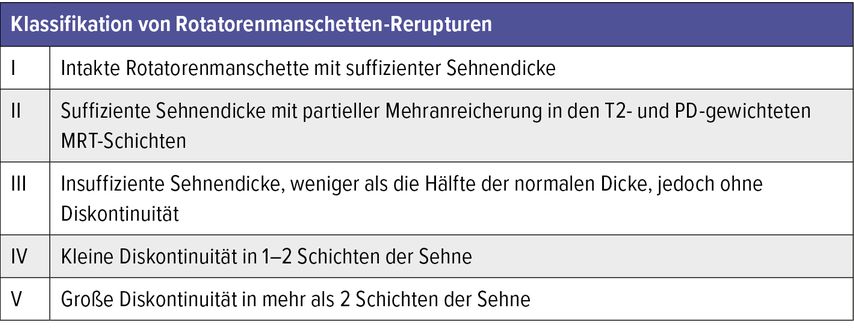

In der Gruppe der Rerupturen konnte außerdem eine Progression der strukturellen Veränderungen – auch im angelagerten Muskel (ISP bei SSP-Reruptur) – gezeigt werden. Diese fettige Degeneration korreliert dabei signifikant mit dem klinischen Outcome.39 Die Klassifikation von Rotatorenmanschetten-Rerupturen erfolgt typischerweise nach Sugaya und unterscheidet fünf Typen (Tab. 1).40

Tabelle 2 zeigt die Übersicht der essenziellen Therapieoptionen bei Rezidiven oder Rotatorenmanschetten-Sehnendefekten.

Tab. 2: Essenzielle Therapieoptionen bei Rezidiven oder Rotatorenmanschetten-Sehnendefekten, um die bestmögliche Behandlungsstrategie auf Grundlage der aktuellen wissenschaftlichen Erkenntnisse auszuwählen (basierend auf der verfügbaren Evidenz). A: Gute Evidenz aus Level-I-Studien, um eine Intervention zu empfehlen oder abzulehnen. B: Mäßige Evidenz aus Level-II- oder -III-Studien, um eine Intervention zu empfehlen oder abzulehnen. C: Schwache Evidenz aus Level-IV- oder -V-Studien, um eine Intervention zu empfehlen oder abzulehnen